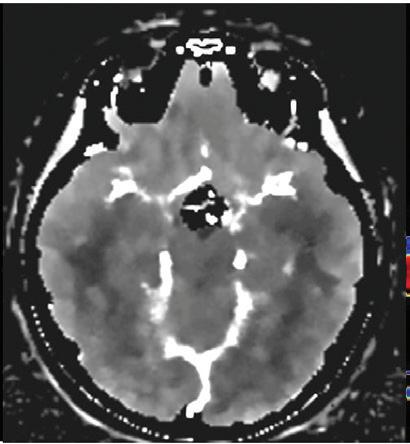

Unenhanced cranial CT of a 55-year-old patient in conventional image and virtual monoenergetic image reconstruction at 40 keV. Note that gray-white matter differentiation is clearly superior in 40 keV images.

Conventional Virtual monoenergetic 40 keV Clinical case collection